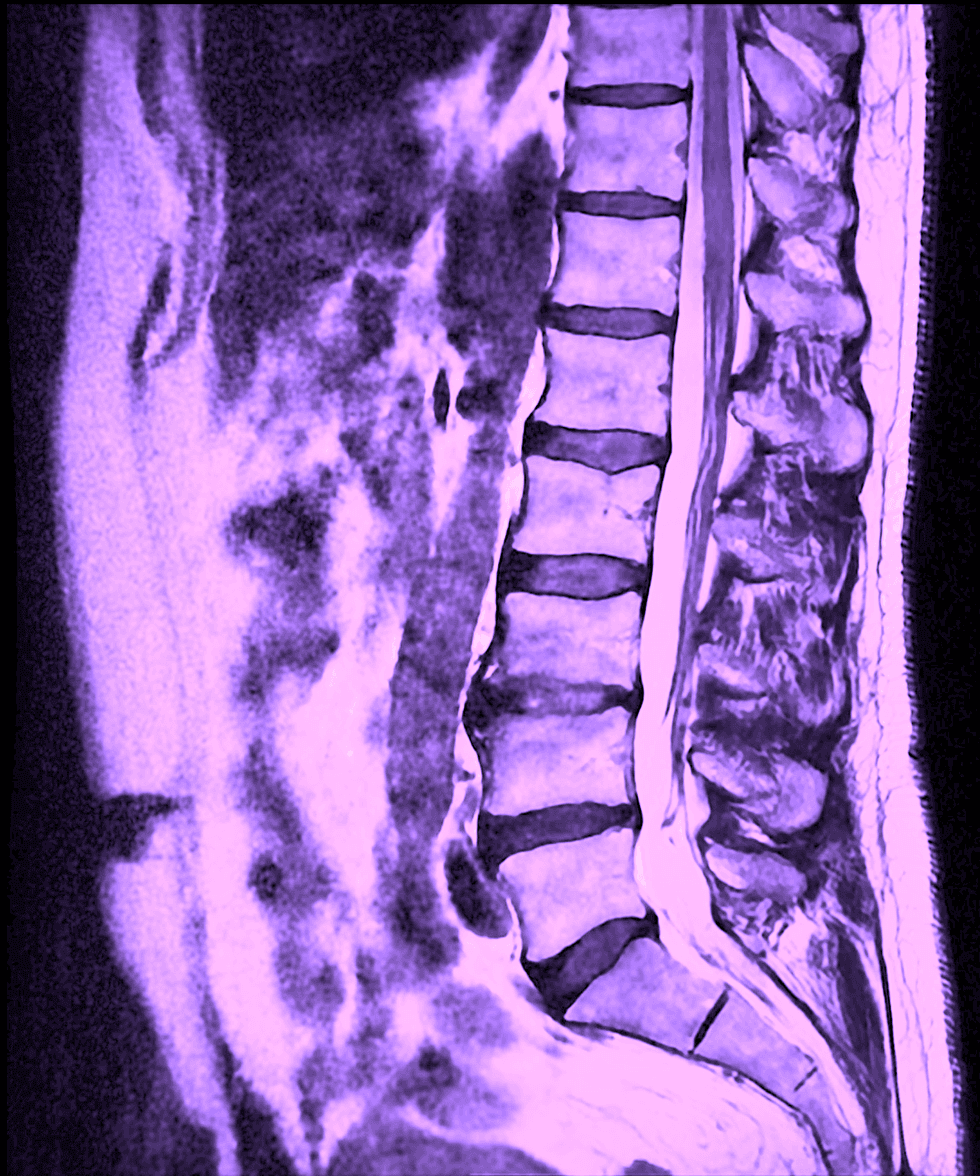

En MR av ländryggen är en avancerad, helt strålningsfri metod som ger mycket detaljerade bilder av ryggradens mjukdelar. Undersökningen använder ett starkt magnetfält och radiovågor för att avbilda diskar, nervrötter, ryggkanal, leder och omgivande mjukvävnad. Eftersom att magnetkameran är särskilt bra på att visa mjukvävnad används undersökningen ofta när man vill bedöma om ryggsmärta beror på nervpåverkan, diskförändringar eller andra strukturella orsaker som inte syns på vanlig röntgen.

En MR-undersökning av ländryggen används främst för att kartlägga strukturella förändringar som kan förklara smärta eller neurologiska symtom. Vanliga fynd inkluderar diskbråck, vilket innebär att en del av diskens mjuka kärna buktar ut. Detta kan, men behöver inte, medföra tryck mot en nervrot. Undersökningen visar även förträngningar i ryggkanalen (spinal stenos) samt kan också visa åldersrelaterade förändringar i diskar och leder, såsom diskdegeneration eller artros i facettlederna. I vissa fall kan MR även avslöja inflammation, infektion, frakturer, tumörer eller andra ovanligare tillstånd som kräver vidare utredning eller behandling.